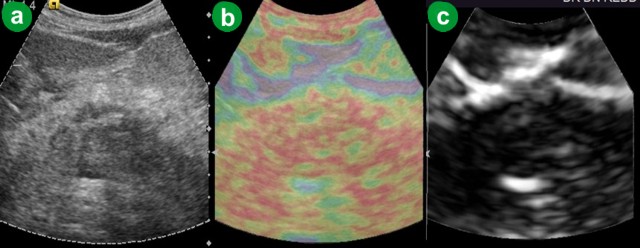

In five patients (7.4% out of the 68 patients) the ARFI-VTQ values for pancreatic parenchyma and peripancreatic fat during the acute attack, or soon following an attack, were greater than the upper detection limit (ARFI-VTQ equal to 4.95 m/s) showing that the tissue hardness of this condition often is beyond the capacity of the machine. The 4.95 m/s value was arbitrarily assigned to these patients in order to allow the analysis of data. After considering this assumption, the ARFI-VTQ values for the pancreatic parenchyma ranged between 1.48 and 4.95 m/s with a mean of 3.283±0.852 m/s (Table 2, Figure 1). The mean ARFI-VTQ value for peripancreatic fat in this group was higher than 2.0 m/s. The eSie touch image colors ranged from light gray to dark black (scores 2-6) on gray scale (Figure 5). On color scale, the images ranged from yellowish green to dark red (scores 2-6) (Figure 5). Out of the 68 patients of this group, 48.5% (n=33) belonged to score 4 (yellowish red image), 35.3% (n=24) belonged to score 5 (patchy red image), 8.8% (n=6) had score 6 (dark red image), 1.5% (n=1) had score 3 (yellow image) and 5.9% (n=4) belonged to score 2 (yellowish green image).

Figure 5. Acute pancreatitis. a. US B-mode image. b. eSie touch color scale image (dark red: score 6). c. eSie touch gray scale image (dark black: score 6). |

Three of our cases were diagnosed as acute autoimmune pancreatitis: one focal (Figure 7) and two diffused. The eSie touch images were dark black (score 6) and dark red (score 6) on gray and color codes, respectively. Post-steroid therapy scan of a patient six weeks following therapy showed decreased ARFI-VTQ to less than 2 m/s. The eSie touch image (Figure 8) was light gray (score 2) on gray scale and yellowish green (score 2) on color scale.

Figure 7. Focal autoimmune pancreatitis. a. US B-mode image show bulky head of pancreas. b. eSie touch color scale image (dark red area in the head of the pancreas: score 6). |

Figure 8. Focal autoimmune pancreatitis six weeks after steroid therapy. a. US B-mode. b. eSie touch color scale image (yellowish green: score 2). |